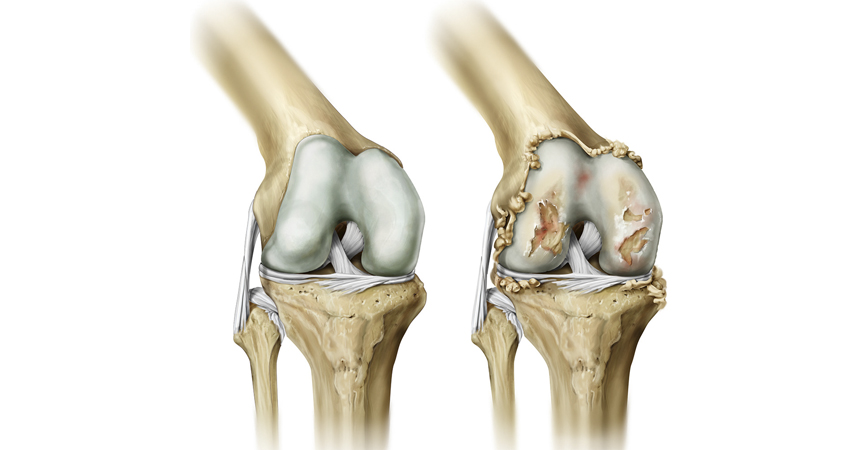

Анатомические рисунки суставов человека